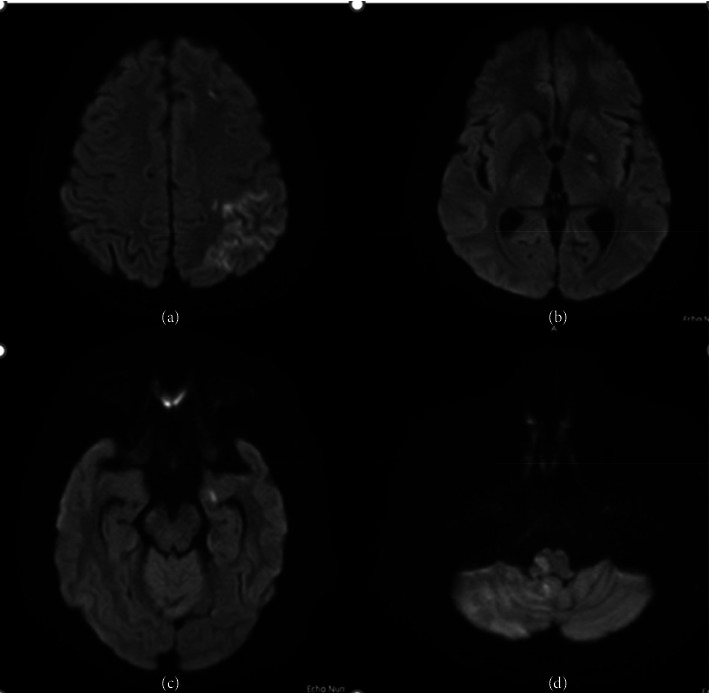

Corrigendum to "Cardioembolic Stroke Due to Prosthetic Valve Endocarditis Caused by <i>Candida parapsilosis</i>: A Case Report".

Corrigendum to "Cardioembolic Stroke Due to Prosthetic Valve Endocarditis Caused by Candida parapsilosis: A Case Report".

[This corrects the article DOI: 10.1155/2024/5581547.].